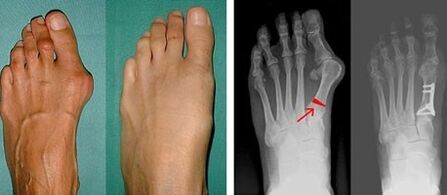

In the first stage of identifying valgus in the big toe and big toe, the doctor performs a visual examination.In this way, it determines the stage of development of the pathology.To identify detailed changes in the joints, x-rays and plantography are prescribed.

If the visual examination and x-rays do not give any results, the patient is referred for plantography to determine possible flat feet.This method involves taking impressions of the feet, from which shoes or insoles with orthopedic properties are made for the patient.The patient is then prescribed podometry.This method uses computer analysis to determine the pressure of a person's weight on the feet.The results of advanced diagnostics are the basis for choosing a treatment method for curvature of the first and second toes.

The disadvantage of radiographic examination is the need to irradiate the patient's legs, which many patients do not like.They think this is a very harmful method.In this regard, effective treatment of hallux valgus cannot be started without the results of plantography.